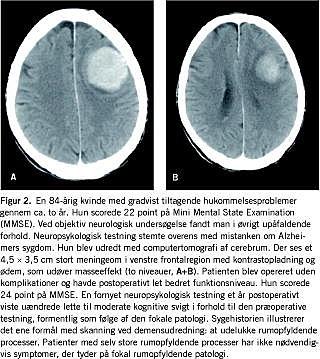

Sammenligner man forekomsten af operabel patologi i ÅS og RH på 4% med tidligere studier findes der god overenstemmelse mellem denne opgørelse og opgørelser fra andre demensklinik/ambulatoriebaserede studier, hvor forekomsten varierer mellem 1% og 4% [2, 3]. Disse studier viste - i overensstemmelse med dette studie - en forekomst af operable tilstande, hvor operation har hel eller delvis effekt på omkring 2% [2, 3]. Selv om påvisning af operabel patologi ikke medfører operation eller remission efter operation, har påvisningen dog betydning for information, rådgivning og behandling (Figur 2 ).